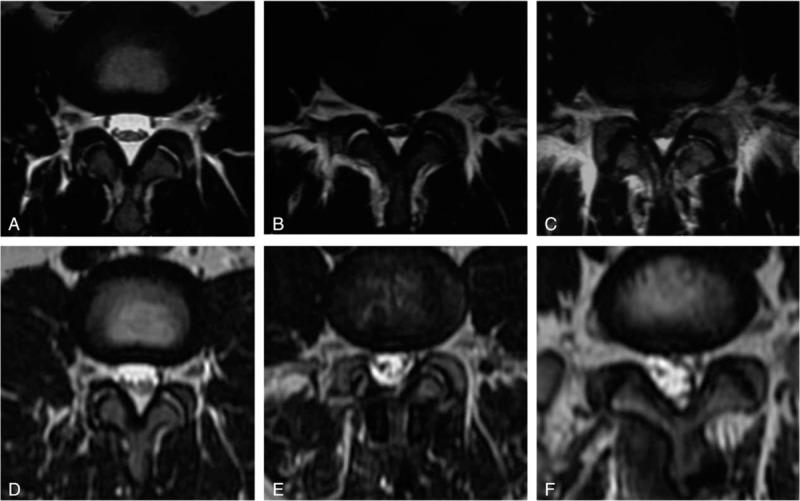

Adjacent segmental degeneration (ASD) is a major issue after pedicular fixation. This study examined the degeneration of the adjacent levels due to the insertion of the Wallis interspinous stabilization system compared with discectomy, using magnetic resonance imaging (MRI).Thirty-eight patients diagnosed with lumbar degeneration disorders at L4-L5 were reviewed: 19 patients underwent discectomy and Wallis system implantation (group A), and 19 patients underwent discectomy (group B). The Visual Analog Scale (VAS) and Oswestry Disability Index (ODI) were assessed preoperatively and postoperatively. ASD was evaluated by MRI.There was no difference in the preoperative ODI scores between the 2 groups (non-normal distribution, median, 50 (40, 50) vs 50 (50, 50), P = .331), but the postoperative ODI scores were different (non-normal distribution, median, 0 (0, 32) vs 20 (20, 30), P < .005). Similar results were observed for VAS. In group A, ASD occurred in 4 patients (21.1%) in the disc and 8 (42.1%) in the facet joint at L3/4, and in 4 (21.1%) in the disc and 5 (26.3%) in the facet joint at L5/S1. In Group B, ASD occurred in 3 patients (15.8%) in the disc at L3/4, and in 4 (21.1%) in the disc at L5/S1. In general, there was no difference between the 2 groups (P > .05), except at L3/4 (P = .015).ASD of the facet joint in the cranial segment occurred after Wallis system implantation, suggesting that the Wallis system cannot prevent ASD of the facet joint, but could have some other benefits for the discs.